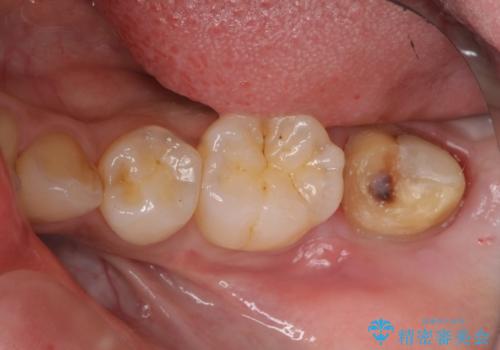

- 左下の7番の虫歯がしみるとのことで来院。

昔他院で虫歯治療した際、「次に虫歯になったらもうきちんとは治せない」と言われたとのことでした。

他院でつめていたものは、セメントで、一時的な詰め物がなされていました。(中は虫歯になっていました。)

虫歯を取ると、歯ぐきの奥深くまで虫歯になっており、そのままではきちんと修復することが難しい状態でした。